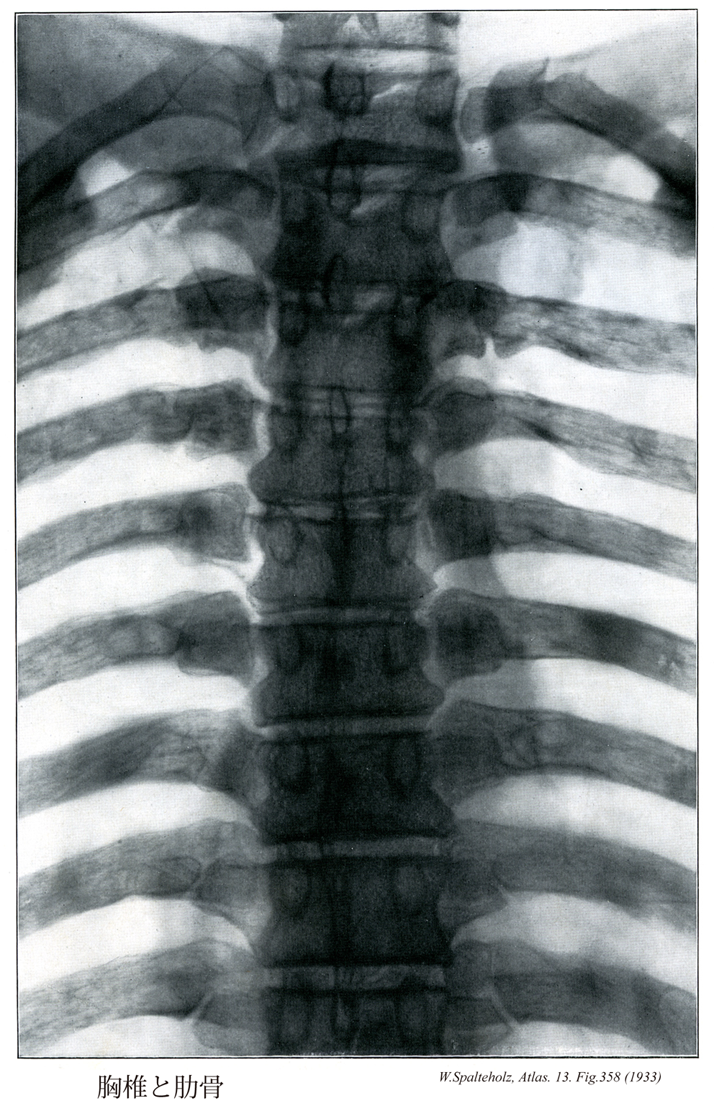

【Thoracic vertebrae [TI-TXII]

胸椎[T1-T12]

Vertebrae thoracicae [T I-T XII]】 The twelve thoracic vertebrae.

→(胸椎は頚椎につづく12個の椎骨で、肋骨と結合して胸郭を形成する。椎体は下位のほど大きい。また、椎体の高さは頚椎より高く、腰椎より低い。椎体の外側面後部には肋骨頭に対する関節窩、すなわち、肋骨窩があり、第二~第九胸椎では椎体の上縁と下縁にそれぞれ半円形の上肋骨窩、下肋骨窩がある。第一~第九胸椎では互いに隣り合う胸椎の下および上肋骨窩が1個の関節窩を作り、一個の肋骨頭と関節する。第一胸椎には半円形の下肋骨窩があり、第十胸椎では上関節窩だけが存在する。また、第十一境地では椎体の上縁に、第十二胸椎では椎体のほぼ中央に1個の円形の肋骨窩がある。胸椎の椎孔はほぼ円形をしており、頚椎の椎孔に比してかなり小さい。横突起は第八胸椎でもっとも大きく、これより上位または下位の胸椎では、第八肋骨から遠ざかるほど小さくなる。第一~第十胸椎では横突起の尖端の前面に円形の関節面があり、横突肋骨窩という。第十一および第十二胸椎の横突起には横突肋骨窩はみられない。境地の棘突起は三角柱のような形をしていて、第1胸椎から第八胸椎までは下位になるほど傾斜が強くなる。しかし、その後は次第に傾斜が弱まり、第十二胸椎ではほとんど水平である。)

【Ribs [I-XII]

肋骨[1-12]

Costae [I-XII]】

→(肋骨という名前は、骨質からなる肋硬骨と軟骨質からなる肋軟骨の総称である。肋骨は扁平長骨で、12対あり、後方で胸椎と連結して胸郭を構成する。軟骨性骨として発生するが、前方の小部分が肋軟骨として軟骨のまま残る。第一~七肋骨は前端が胸骨外側縁と連結しているが、第八から十二肋骨は胸骨に達していない。前者が真肋、後者が仮肋である。仮肋のうち第八~第十肋骨では、肋軟骨が上位の肋軟骨と結合して肋骨弓を形成する。第十一・第十二肋骨は自由端で終わる(浮遊肋骨)。肋骨は後上方から前下方へ向かい、胸骨近くで角をなし、上方へ向かう。第一・第二肋骨では肋軟骨との境界部で、他の肋骨では肋軟骨部で曲がっている。長さは第一肋骨~第七肋骨まで増加し、第八肋骨以下では減少する。胸椎体と連結する膨大した部分が肋骨頭で、肋骨頭関節面がある。第二~第十肋骨では水平に走る肋骨頭稜によって、上位胸椎体の下肋骨窩に対する上方の小さな関節面と、各肋骨と同順位の胸椎体の上肋骨窩に対する下方の大きな関節面とが区別される。第一・第十一・第十二肋骨では、肋骨と同順位の胸椎体とのみ連結するので、肋骨頭関節面は単一な平面である。肋骨体に続く前後にやや扁平な部分がが肋骨頚で、各肋骨と同順位の胸椎横突起の前面に位置している。鋭い上縁が肋骨頚稜で、後面は粗面をなす。外側端後部外面の膨隆した部分が肋骨結節で肋骨体との境をなす。肋骨結節には、各肋骨と同順位の胸椎横突起に対する下内側部の肋骨結節関節面と、外側部の靱帯が付着する隆起とがある。肋骨結節に続く扁平な部分が肋骨体で、上縁は丸く下縁は鋭い。肋骨結節の外側で、前後にやや厚く後面が粗面をなし、肋骨がやや強く弯曲する部分が肋骨角である。第一肋骨の肋骨角は肋骨結節の所にあるが、第二肋骨以下下方の肋骨ほど、肋骨角は肋骨結節の外側方に位置するようになる。肋骨体内面下部で、肋骨頚から前方に走る溝が肋骨溝で、肋間神経・肋間動静脈が入る。溝は前端近くで不明瞭となる。肋骨体の前端は被厚し、断端は楕円形の凹面として終わる。肋骨は内側方へ屈曲するとともに、長軸のまわりで上縁が内側方向へねじれている。第三から第十肋骨は上述の一般的形態を示すが、第一・第二・第十一・第十二肋骨はやや変形を示す。第一肋骨は最も短く、上下に扁平なため幅が最も広い。肋骨角に相当する部分は肋骨結節に一致し、ここで弯曲が最も強い。上面の中央内縁に近い部分の小隆起が前斜角筋結節で、この前方にある浅い陥凹が鎖骨下静脈溝、後方の浅い陥凹が鎖骨下動脈溝である。第二肋骨の上面中央外側部の粗面が前鋸筋粗面である。)